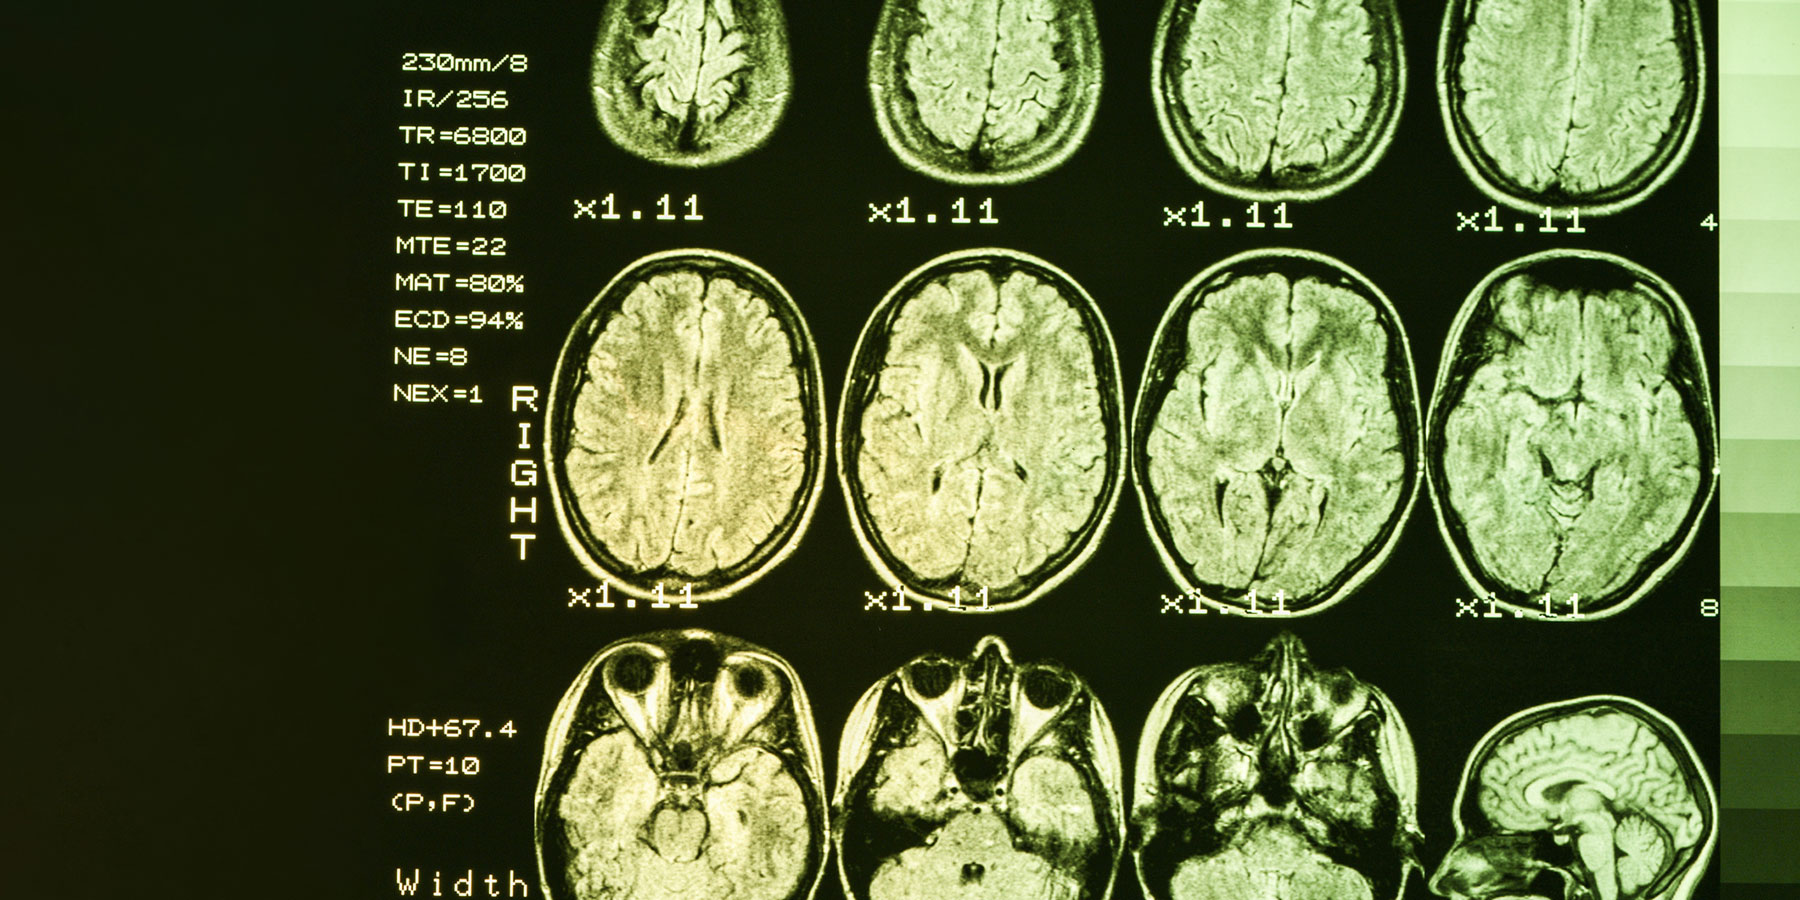

Alzheimer's disease is a neurodegenerative disorder that involves worsening dementia and the formation of protein plaques and tangles in the brain. The hippocampus, part of the brain involved in memory, is one of the first regions to sustain damage. To better understand which genes contribute to the progression of this heritable disease, the researchers identified genes expressed at higher or lower levels in the hippocampus of 111 people with Alzheimer's disease compared to healthy brains.

The research team further validated their findings by comparing gene expression for the two dozen genes to images of the individuals' brains. In Alzheimer's disease, damage and loss of neurons causes the hippocampus to shrink, which can be measured through medical imaging. The researchers established that expression of two of the genes is related to the size of the hippocampus and a diagnosis of Alzheimer's disease.